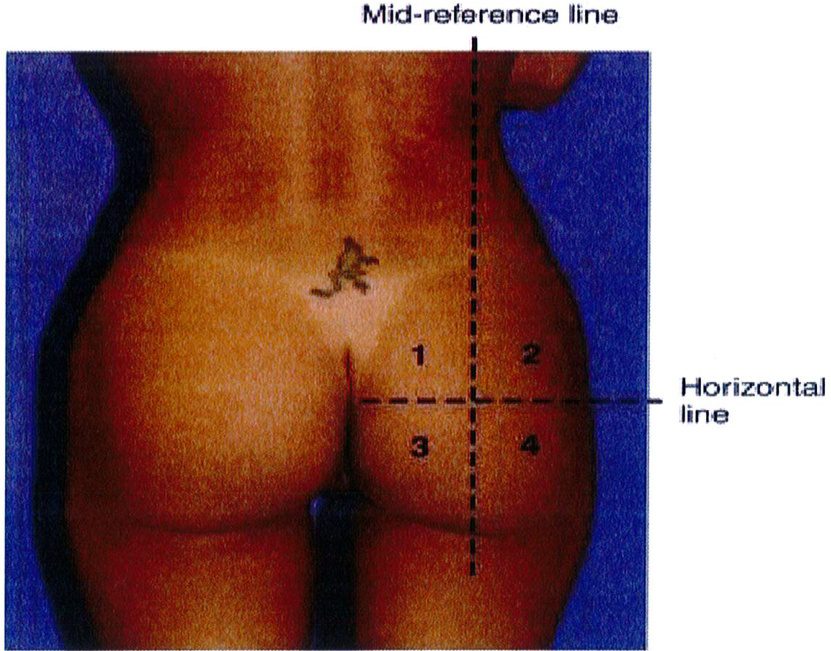

Từ góc nhìn sau – trước

Hãy tưởng tượng cơ mông nằm trên khung chậu với trục đối xứng là đường liên mông. Theo lý thuyết, cơ mông có khối lượng bằng nhau ở hai bên và có hình dạng của 1 quả bóng đá. Để đánh giá kỹ hơn, vẽ một đường nằm ngang (Hình 18). Điều này cho phép chia mông thành 4 góc phần tư: trên trong, trên ngoài, dưới trong và dưới ngoài. Vòng mông lý tưởng là vòng mông phân bố đểu tổ chức ở 4 vùng trên. Khi đánh giá từ góc nhìn sau trước, mỗi góc trong số 4 góc này phải được đánh giá xem chúng bằng nhau hay thiếu so với các góc còn lại như thế nào.

Hình. 18. Hình ảnh 4 góc phần tư: 1: góc trên trong, 2: góc trên ngoài, 3: góc dưới trong, 4: góc dưới ngoài. Nên đánh giá đầy đủ từng góc một.

Gluteal Quadrants: Góc phần tư Mid-reference line: Đường tham chiếu ở giữa mông